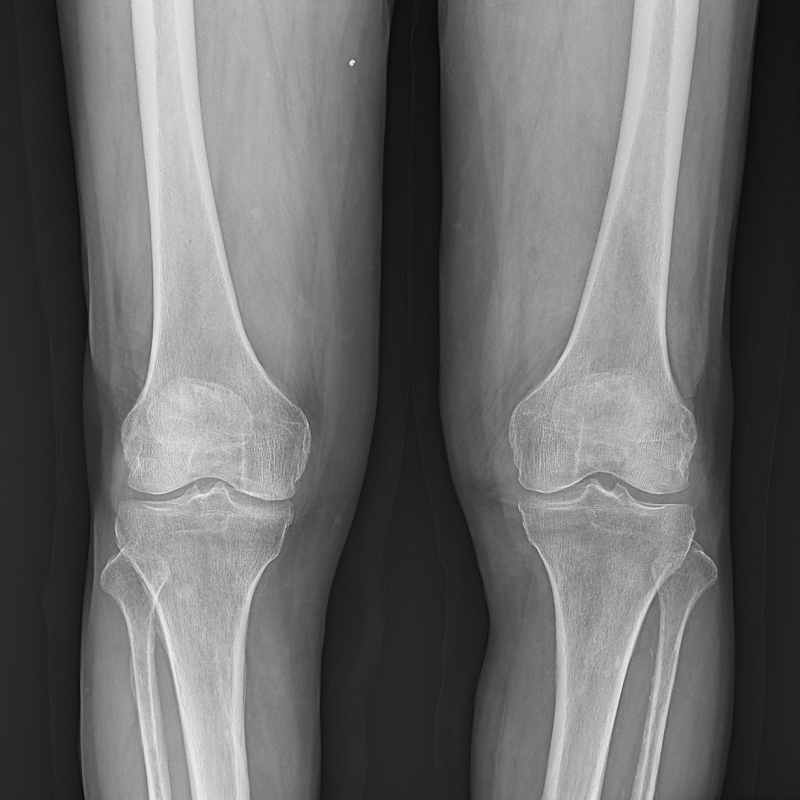

●呈現全下肢或全脊柱圖像

●在脊柱及下肢畸形矯正手術(shù)治療中,為術(shù)前方案制定和術(shù)后復查提供精準測量

●有效解決傳統X光片不能一次成像問(wèn)題,為患者提供更加優(yōu)質(zhì)的醫療服務(wù)